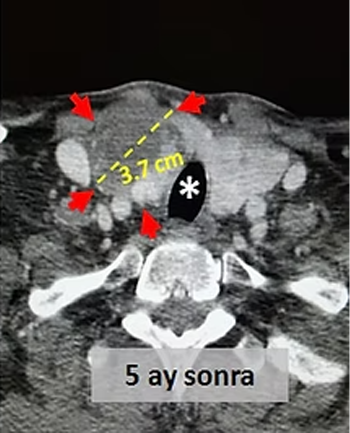

Tiroid sağ lobunda en büyüğü 7cm çaplı, göğüs boşluğuna uzanan nodüller bulunan ve nefes darlığı şikayeti olan hastada, tiroid sağ lobunu besleyen 2 atardamar embolizasyonla tıkanıyor.

Embolizasyondan 5 ay sonra çekilen kontrol tomografilerinde, embolizasyon uygulanan sağ lobun hacimsel olarak yaklaşık %80 küçüldüğü, büyük nodülün çapının 7cm den 3.7cm ye düştüğü (hacimsel olarak %86 azalma), sağlam olan sol lobun (*) büyüdüğü ve kitlelerin soluk borusuna soluk borusuna (*) yaptığı basının azaldığı izleniyor. Hastada, boyundaki şişlik ortadan kalkmış ve işlemden bir ay sonra nefes darlığı tamamen düzelmiştir.